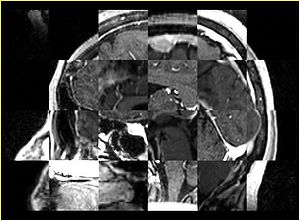

• Checkerboard appearance of unregistered images for the representative data of interest

• Case03